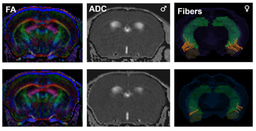

Distinct early development trajectories in Nf1± and Tsc2± mouse models of autism - Journal of Neurodevelopmental Disorders

Background Autism spectrum disorder (ASD) is a neurodevelopmental condition characterized by deficits in social communication and interaction, and repetitive behaviors. Males are three times more likely to be diagnosed with ASD than females, and sex-dependent alterations in behavior and communication have been reported both in clinical and animal research. Animal models are useful for understanding ASD-related manifestations and their associated neurobiological mechanisms. However, even though ASD is diagnosed during childhood, relatively few animal studies have focused on neonatal development. Methods Here, we performed a detailed analysis of neonatal developmental milestones and maternal separation-induced ultrasonic vocalizations (USVs) in two genetic animal models of ASD, neurofibromatosis type 1 (Nf1±) and tuberous sclerosis complex 2 (Tsc2±). Results Nf1± and Tsc2± mice display strikingly distinct developmental profiles regarding motor, strength, and coordination skills. Nf1± mouse pups mostly show genotype-related differences, whereas Tsc2± mouse pups mainly present sexual dimorphisms. Furthermore, we found several differences regarding the number of USVs, frequency modulation, and temporal and spectral profile. Importantly, Nf1± animals tend to present sex- and genotype-dependent differences earlier than the Tsc2± mouse pups, suggesting distinct developmental curves between these two animal models. Conclusions This study provides a nuanced understanding of how these two ASD models differ in their developmental trajectories. It underscores the importance of studying sex differences and early-life developmental markers, as these could offer crucial insights into ASD’s progression and neurobiology. The distinct profiles of these models may help guide more targeted therapeutic strategies in the future.

ASD is not one single condition but a spectrum, and genetics plays a big part in its diversity. For example, syndromes like neurofibromatosis type 1 (NF1) and tuberous sclerosis complex type 2 (TSC2) are both associated with a higher likelihood of ASD, but they affect different biological pathways. Indeed, while NF1 is characterized by reduced excitability, TSC2 shows an increase in the E/I ratio of neuronal excitation. So, we wanted to know: do these genetic differences translate into differences in early development?

Looking at the very beginning

What we found was striking: Nf1+/- and Tsc2+/- pups showed very different developmental profiles. In Nf1+/- pups, we observed clear genotype-driven differences early on, while Tsc2+/- pups showed mainly strong sex-dependent differences instead. Even the ultrasonic vocalizations, namely their number, frequency modulation, or call complexity, were distinct. In other words, these two genetic models of ASD start life on very different developmental paths, which translates to distinct motor, coordination and communication skills at each timepoint.